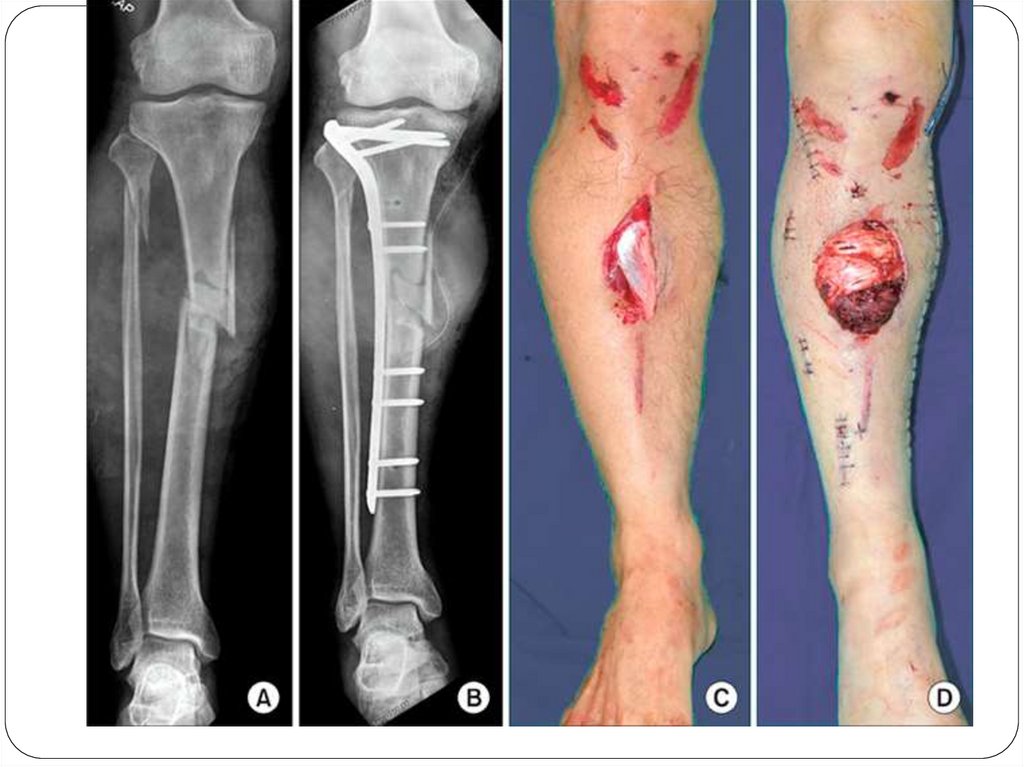

III. По состоянию кожных покровов и

слизистых:

1. Закрытые - без повреждения кожи и

слизистых.

2. Открытые - с повреждением

кожных покровов и слизистых.

ОПЕРАТИВНОЕ ЛЕЧЕНИЕ ПЕРЕЛОМОВ

Оперативное лечение перелома

предусматривает одномоментную

открытую (чаще) или закрытую (реже)

репозицию костных отломков и их

прочную фиксацию – остеосинтез.

Накостный остеосинтез – фиксация отломков

осуществляется при помощи пластины,

закрепляемой винтами на поверхности кости.